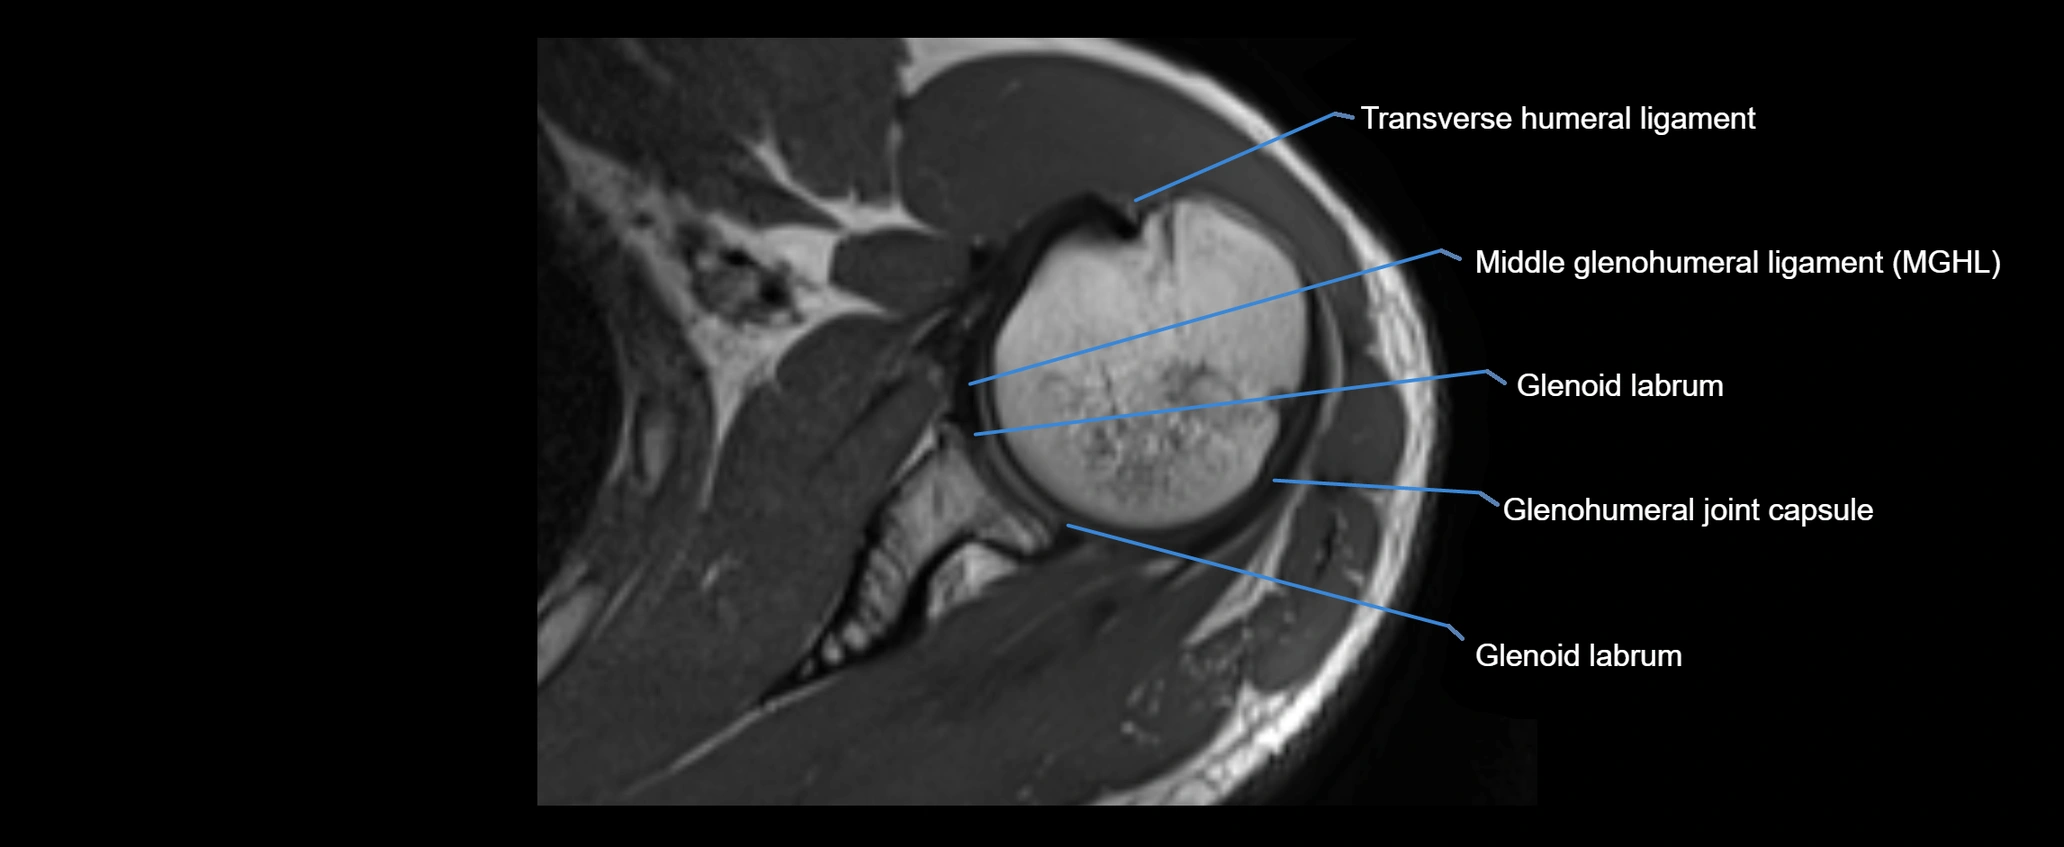

MRI images

image